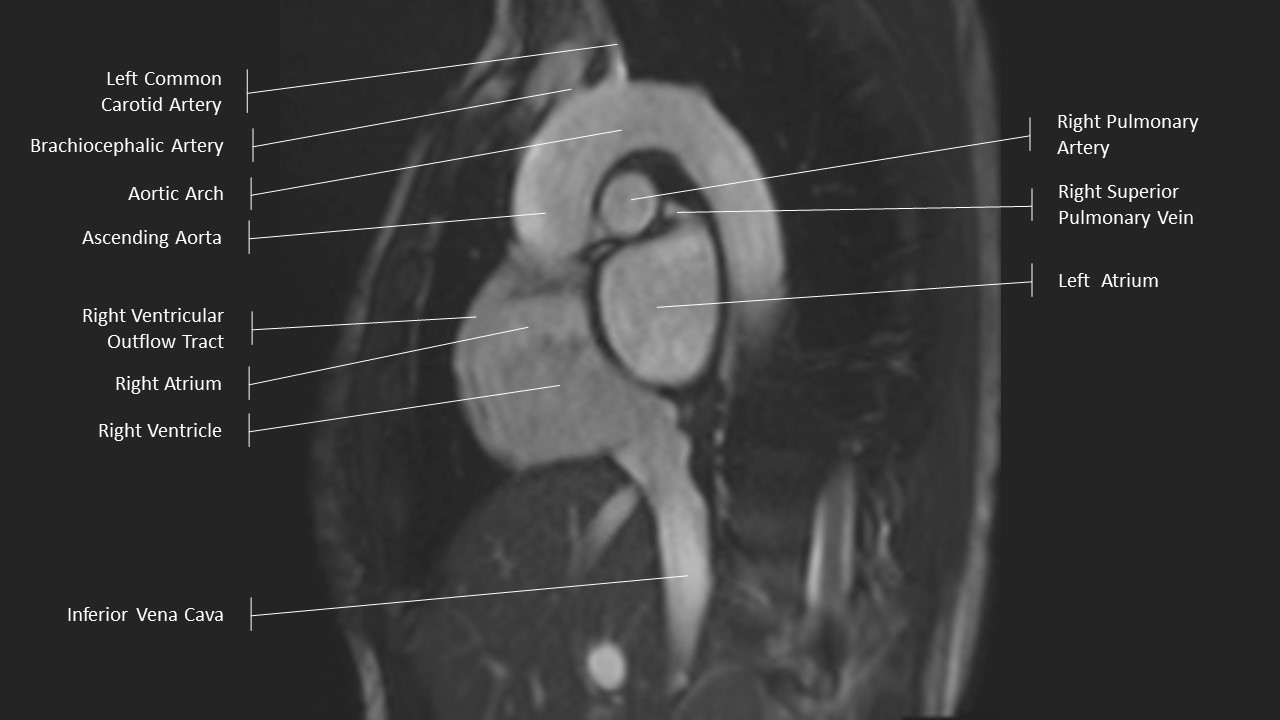

Aortic Arch Series